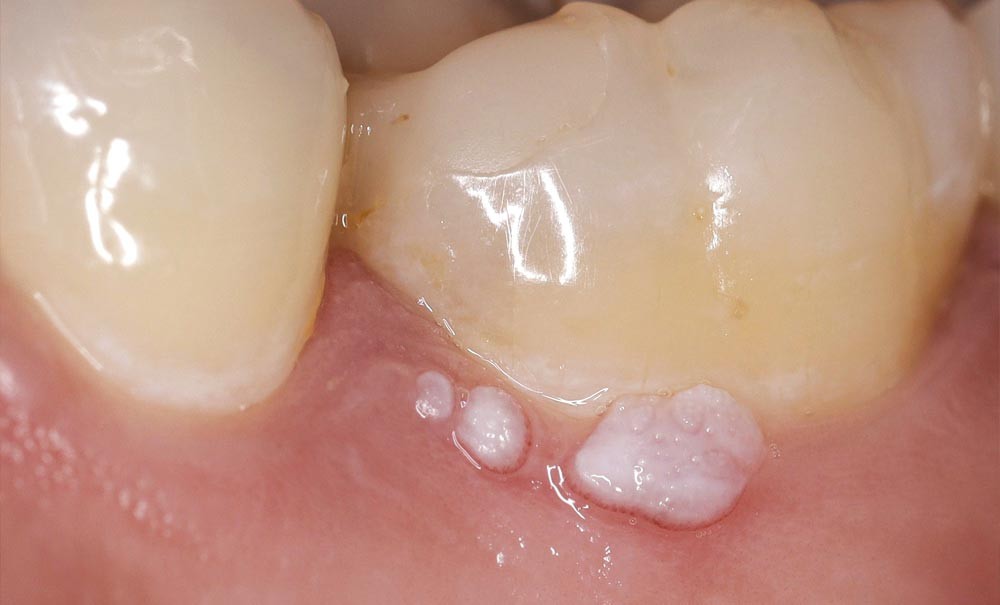

Image commentée : une petite boursouflure

• Anamnèse. Une patiente âgée de 26 ans consulte sur les conseils de son chirurgien-dentiste traitant, lequel a remarqué une petite « boursouflure blanche » asymptomatique au niveau de 36, apparue, aux dires de la patiente, quatre ans auparavant. La patiente est en bonne santé générale, sevrée du tabac depuis six ans. Elle ne prend aucune médication et ne présente aucun antécédent médical.

• Examen clinique. Il n’existe pas d’adénopathie. L’examen endo-buccal révèle la présence de trois petites végétations blanches (excroissances gingivales circonscrites), de 1 à 3 mm de diamètre, à la surface papillomateuse, sessiles, regroupées au niveau du collet vestibulaire de 36. Il n’existe pas de lésions de ce type sur les autres muqueuses orales.